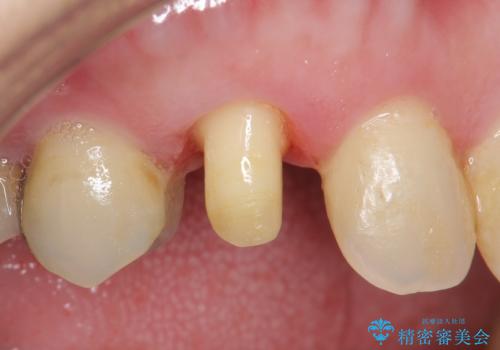

- 他院にて根管治療を行ったが疼きが治まらないため、当院にいらっしゃった方の症例です。

再根管治療を行い症状が治まったのを確認後、オールセラミッククラウン(スペシャル)による補綴を行いました。